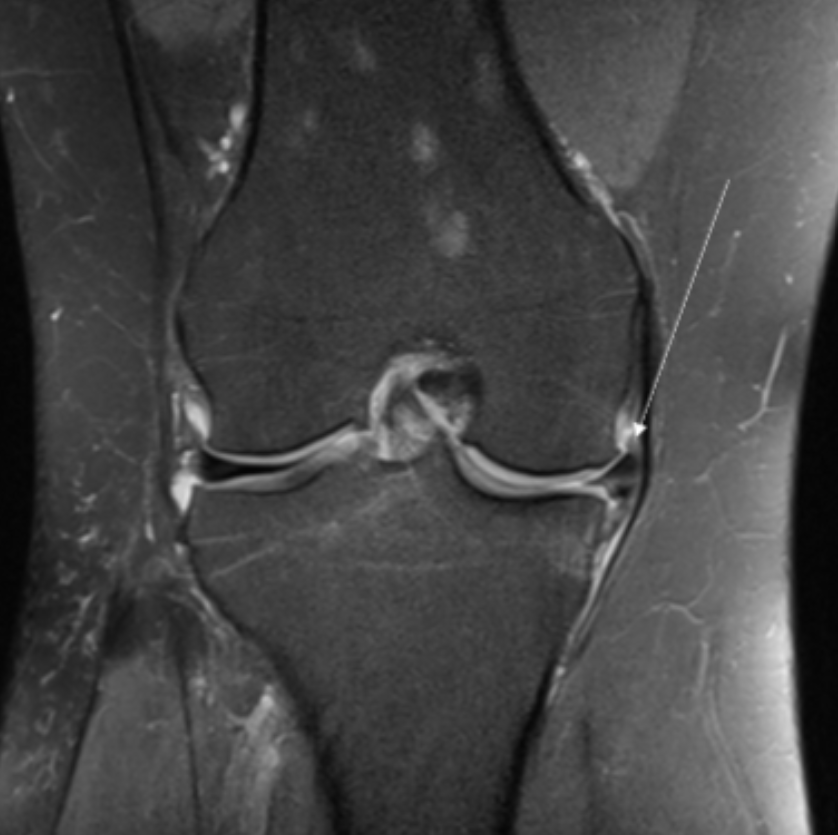

Describe the pathology indicated by the arrow (Cor PD FS).

Medial meniscal tear